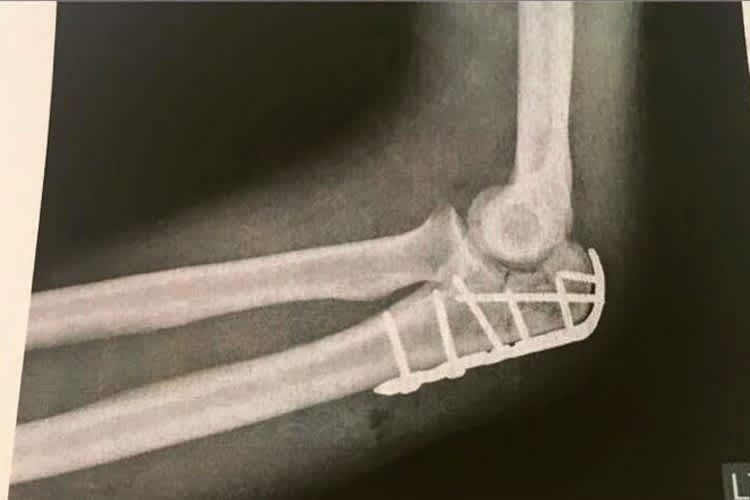

Vergangenen Donnerstag hatte sich Bastien Mackels mit seiner IDM-BMW bei einem Testtag auf seiner Heimstrecke im belgischen Zolder bei einem mysteriösen Sturz den Ellbogen und einen Knochen in der linken Hand gebrochen. Am Dienstag dieser Woche wurde er erfolgreich operiert.

"Der Arzt war mit seiner Arbeit sehr zufrieden", beschreibt Mackels das OP-Ergebnis einen Tag später. Die Ärzte gehen von einer Rehabilitations-Zeit von sechs Wochen aus. Damit ist neben dem Langstrecken-WM-Einsatz am kommenden Wochenende in Le Mans auch der IDM-Saisonauftakt auf dem Lausitzring gestrichen. Mackels war dennoch froh, als die OP rum war, denn ganz schmerzfrei verlief der Eingriff nicht. Gerade Mal 24 Stunden später kann Mackels das Krankenhaus schon wieder verlassen. "Ich möchte mich für all die Unterstützung und die Genesungswünsche, die mich erreicht haben, bedanken", versichert der Belgier.